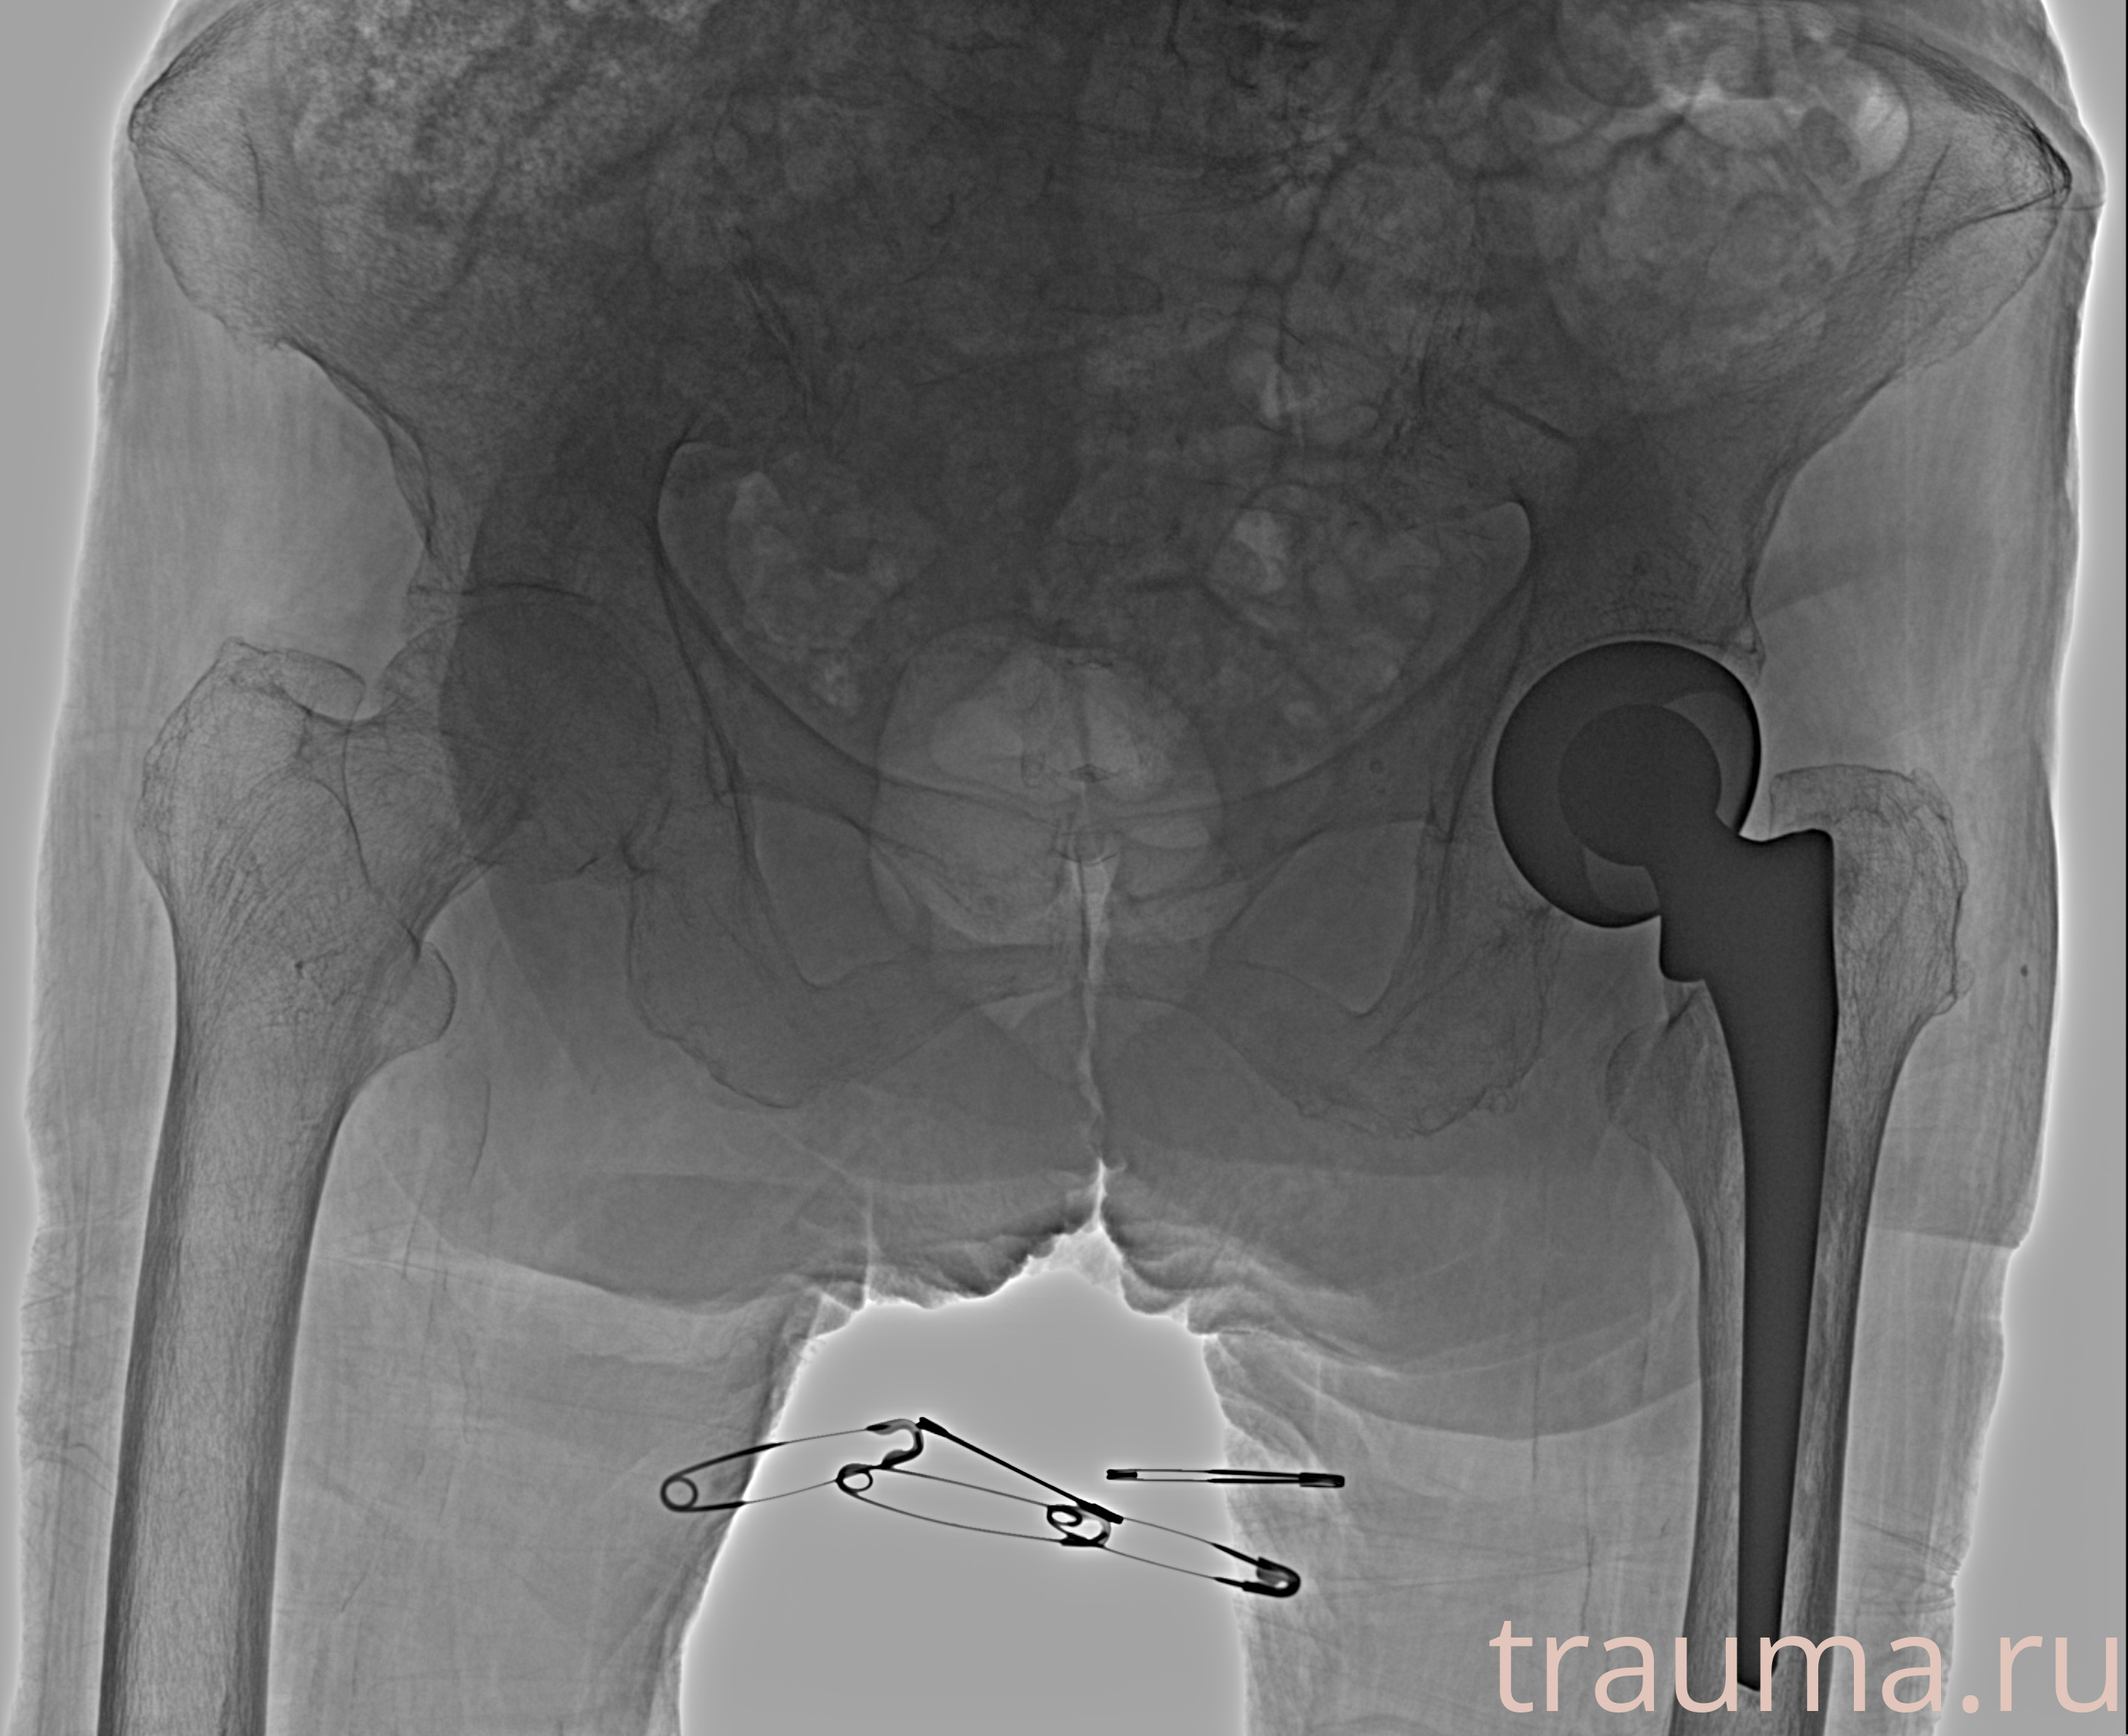

Рентген на дому: по вашему адресу приезжает врач-рентгенолог, травматолог-ортопед с мобильным рентгеновским аппаратом, проводит диагностику травмы или заболевания, делает необходимые рентгенограммы, дает рекомендации по дальнейшему лечению. Получить качественные снимки в домашних условиях возможно благодаря уникальной методике, разработанной МосРентген Центром для института  Склифосовского